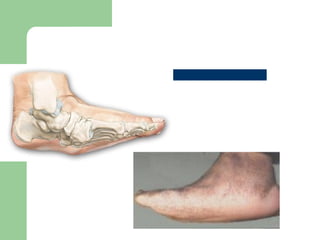

Presentation

 DEPENDS OF DURATION OF DISEASE

 Mild swelling w/o deformity-Moderate

deformity with extreme swelling.

 Signs of inflammation.

 Profound unilateral swelling. WBC and

ESR may

be normal

 Increase in localized

temp

 Erythema,

 Joint effusion.

 75% pt. have pain.

 The deep tendon

reflexes at the knee are

absent in a majority of

patients.

• #36 ROCKERS BOTTOM DEFORMITY:-a convex deformity of the foot’s plantar aspect caused by the collapse of metatarsal bones